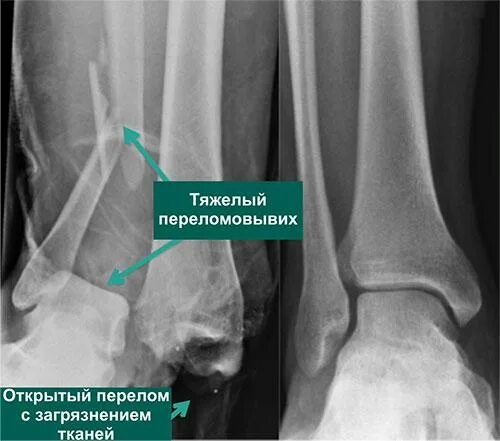

Подвывих сухожилия